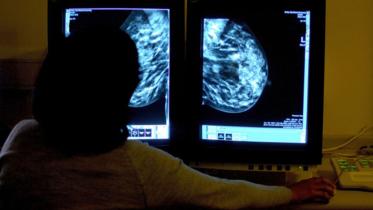

Skipping your mammogram? Here’s why that’s a terrible idea

October marks Breast Cancer Awareness Month. The significance of this month varies from person to person — for some, the pink ribbon is a memory of a disease that changed their lives, while for others, it is an opportunity to rally behind almost two million women who get cancer diagnoses annually throughout the globe.

28 October 2024, 10:29 AM

The month of October and pink ribbons displayed almost everywhere brings a certain sense of apprehension amongst people who have loved ones suffering from breast cancer. Yet, with all the discomfort associated with the universal advertisements, there’s a major encouraging side to it — people become more conscious about early screening and medical procedures that can prevent cancer from taking root in the first place.

No need for chemo in many breast and lung cancers, major studies show

Two major studies show that many people with breast and lung cancers may forgo chemotherapy and still live longer, signaling a waning need for what was long seen as the standard of cancer care.